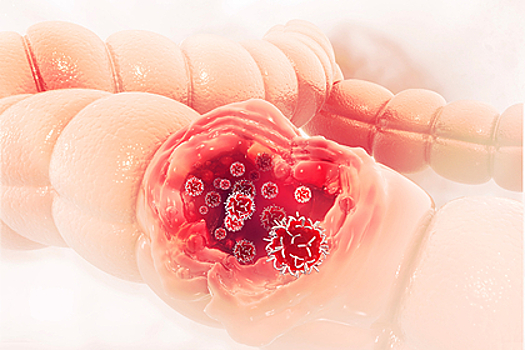

Жидкий стул, болезненное газообразование и спазмы живота могут свидетельствовать о развитии рака толстой кишки, сообщили врачи Фариха Саридж и Викрам Редди. В беседе с изданием Eat This, Not That! они перечислили явные симптомы опасного заболевания.

Одним из самых очевидных признаков рака толстой кишки колоректальный хирург, доктор медицинских наук Викрам Редди назвал ректальное кровотечение. Он предупредил, что данный симптом также характерен для геморроя, однако стоит обязательно сделать колоноскопию, чтобы исключить онкологический диагноз, особенно если кровотечение долго не проходит.

Другими распространенными симптомами рака толстой кишки являются болезненные газообразования, частые вздутия, беспричинно жидкий стул, спазмы в области живота, а также постоянная усталость и потеря веса, рассказала врач общей практики, доктор медицинских наук Фариха Саридж. По ее словам, также заболевание может сопровождаться тошнотой и рвотой. Эти симптомы могут возникнуть, если опухоль закупоривает кишечник и препятствует прохождению по нему жидких и твердых отходов жизнедеятельности организма или газов, пояснила медик. Также она добавила, что в этом случае человек может страдать от сильных запоров.